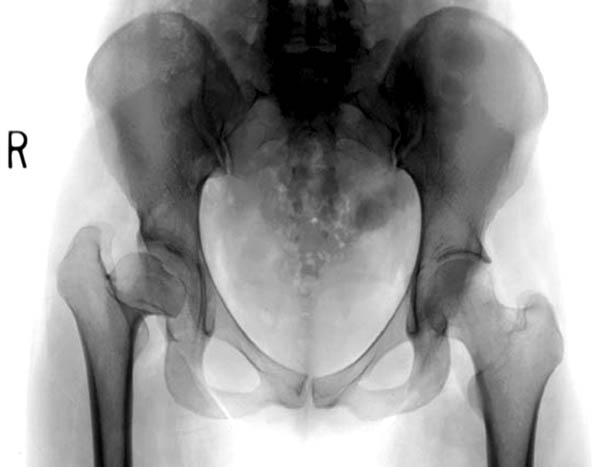

Здесь комбинированная патология тазобедреннего сустава, связанная с высокостоящим вертелом и отсутствием (ротирована?) шейкой. А на стороне вертлужной впадины диспластический сустав. Обычно высоко расположенный вертел приводит к уменьшению силы мышц абдукторов, но отстутствие шейки привело к вертикальному расположению  сил в суставе. Боли появляются из-за вертикального давления, а неровные контуры головки приводят к ограничению движений в суставе. Такое состояние быстро изнашивает сустав, и больные в молодом возрасте заканчивают тотальным протезированием.

Представленный случай имеет схожесть....,  и последний снимок после 2 х лет.